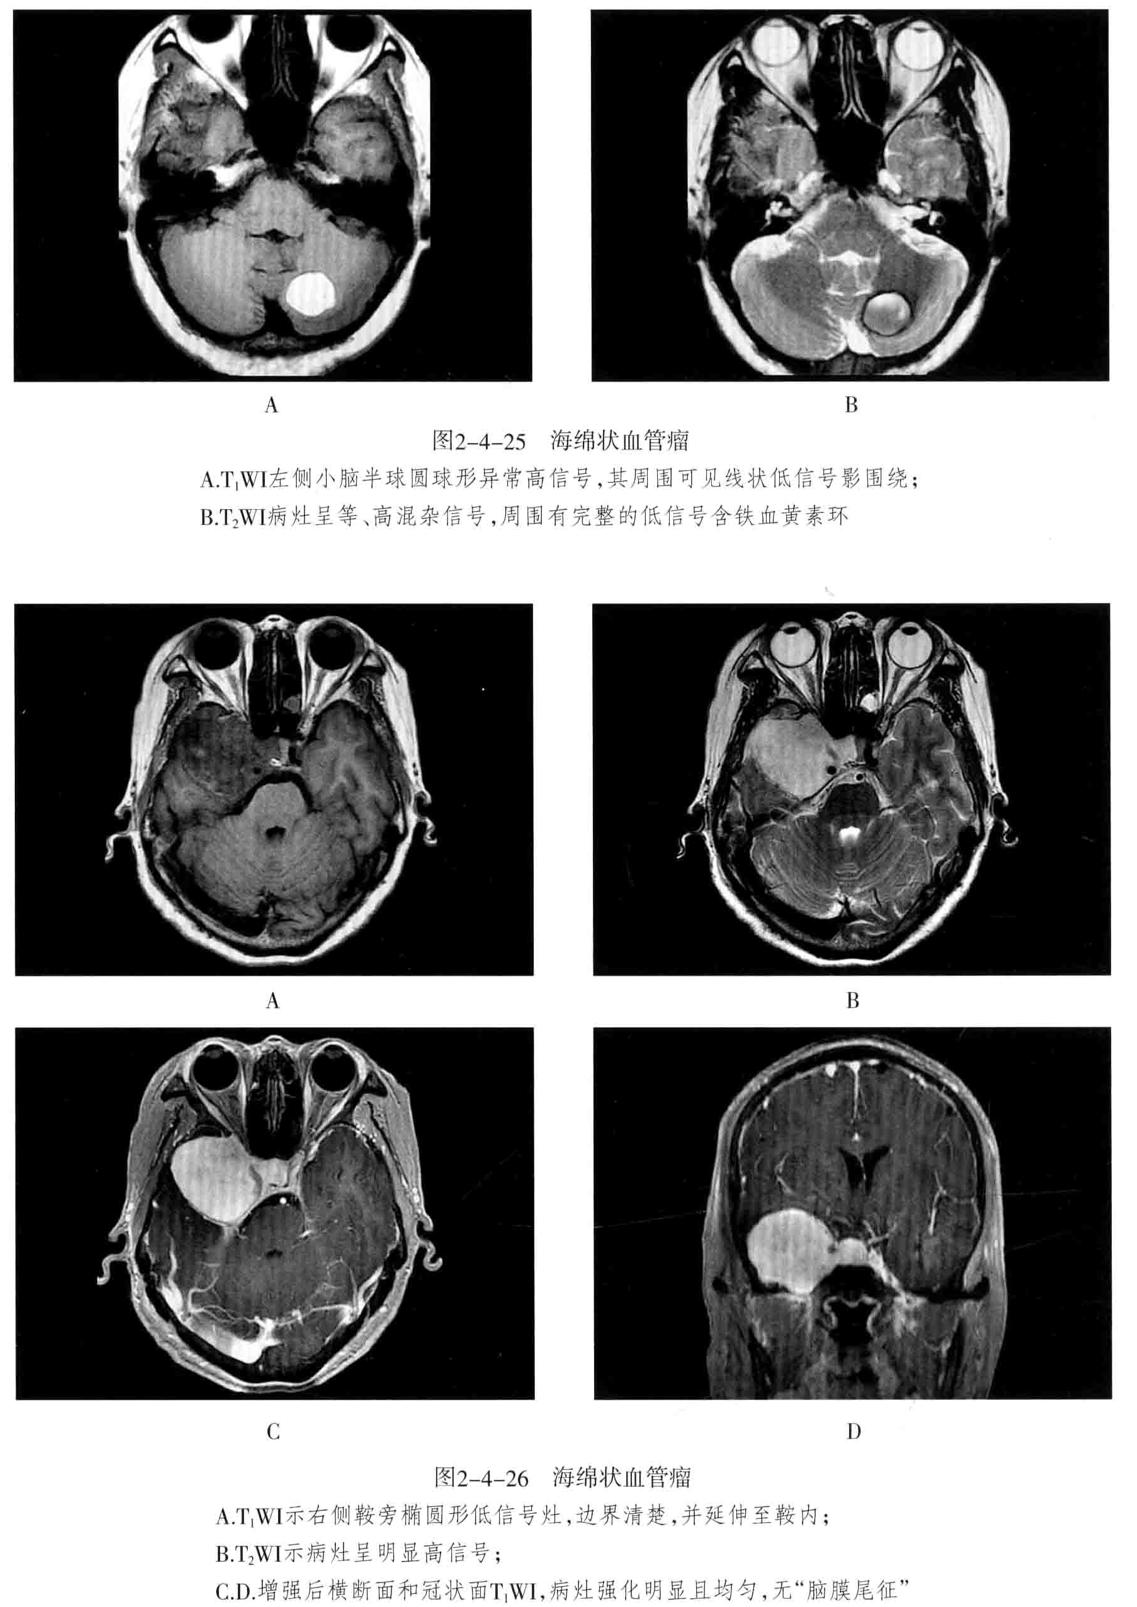

- 海绵状血管瘤 : 病变主要由不规则、大小不等的薄壁海绵状血窦组成,其间有增生的胶质组织,没有正常的神经组织,可反复少量出血,常有不同程度的钙化和含铁血黄素沉着。可发生于脑内(常见于大脑半球各叶)、脑外(常见于颅底)。常无任何症状,或表现为癫痫等。

- MRI检查:T1WI多呈高信号、稍高信号或混杂信号,T2WI上呈高、低混杂信号,典型者呈“爆米花”状,境界清楚,病灶周围有含铁血黄素沉积,T2WI是表现为低信号环。病灶内及周边无流空血管影。病灶无占位效应,周围脑组织无水肿。大量出血时,表现为病灶短期明显增大,可有占位效应。增强后脑内者病灶可轻度强化,亦可无强化。脑外者多于颅底鞍旁,T1WI低信号,T2WI明显高信号,边界清楚,增强后明显强化且强化均匀。